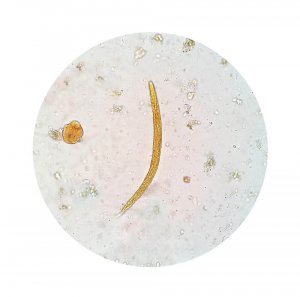

Henkilön todellinen tila saadaan helposti selville ulostetta tutkimalla. Näin voidaan selvittää, onko siinä aktiivisia ameeboja.